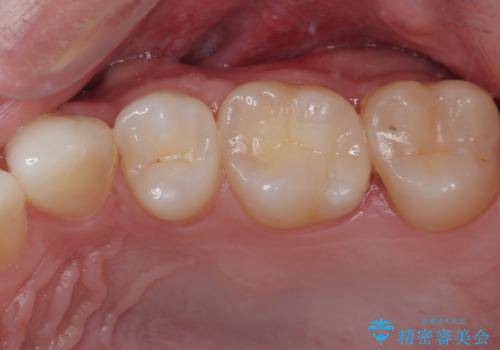

上顎左側第一大臼歯に齲蝕が認められたため、矯正治療終了後に 精度の高いセラミックインレー にて修復治療を行いました。